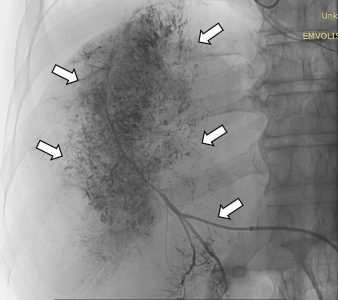

Ο χημειοεμβολισμός είναι μια επικουρική μέθοδος τοπικής θεραπείας για πρωτοπαθή και δευτεροπαθή νεοπλάσματα του ήπατος. Στόχος του επεμβατικού ακτινολόγου είναι η τοπική έγχυση χημειοθεραπευτικού σε κλάδους της ηπατικής αρτηρίας, ώστε να επιτευχθούν υψηλές συγκεντρώσεις τοπικά στην ηπατική εξεργασία χωρίς να προκαλούνται συστηματικές επιπλοκές τοξικότητας του χημειοθεραπευτικού. Επιπλέον, προκαλείται τοπική ισχαιμία-νέκρωση στην περιοχή του όγκου από τα εμβολικά υλικά-μικροσφαιρίδια εμβολισμού, χωρίς να επηρεάζεται το φυσιολογικό ηπατικό παρέγχυμα.

Ο χημειοεμβολισμός έχει καθιερωθεί ως θεραπεία εκλογής στην περίπτωση του ηπατοκυτταρικού καρκινώματος. Ενδείκνυται επίσης σε ηπατικές μεταστάσεις από νευροενδοκρινείς όγκους, καρκίνο παχέος εντέρου και μελάνωμα, σε συνδυασμό με συστηματική χημειοθεραπεία, της οποίας ενισχύει και βελτιώνει τα αποτελέσματα. Ενδείξεις αποτελούν επίσης το χολαγγειοκαρκίνωμα και οι μεταστάσεις από καρκίνωμα νεφρού και σαρκώματα μαλακών μορίων. Οι περισσότεροι ασθενείς μπορούν να επιστρέψουν στο σπίτι τους μία ημέρα μετά τη θεραπεία.